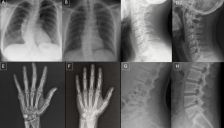

警惕AI深度伪造X光片以假乱真

最新研究发现AI生成的深度伪造X光片能以假乱真,连专业放射科医生和先进AI模型都难以辨别。这项研究揭示了医疗影像伪造可能带来的重大安全风险,包括医疗欺诈和诊断篡改。文章探讨了防范措施,如数字水印和加密技术,并警示AI深度伪造对医疗系统可信度的潜在威胁。